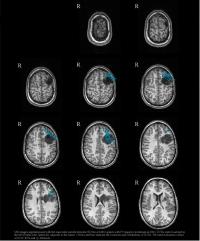

The Webcast will feature Children's intraoperative MRI system, known as the MR-OR, the first and only system of its kind at a pediatric hospital in the country. Developed by IMRIS, the iSPACE surgical imaging suite captures digital images through a unique, ceiling-mounted, movable MRI scanner that can be used to take high-resolution, real-time patient scans before, during and after a surgical procedure. This advanced technology allows surgeons to determine the extent of a tumor while the patient is undergoing surgery to ensure its accurate removal.

MR scans will be used to assess the degree of tumor resection before the surgery is completed.

Dr. Madsen will operate on a patient with oligodendroglioma, a low-grade tumor arising from glial cells in the central nervous system. The tumor lies near motor and sensory areas of the brain, which will require electrocorticography and physiological tests to map the normal brain around the tumor before the surgery. Once the mapping has been completed, Dr. Madsen will then perform a microsurgical resection of the tumor.